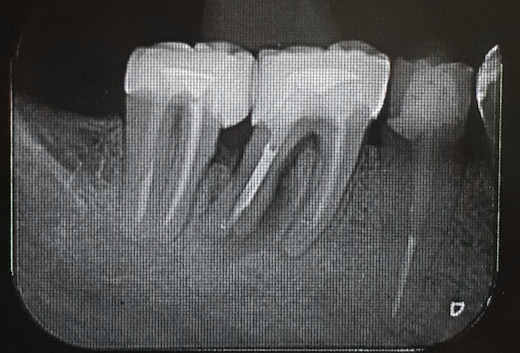

Uma paciente de 62 anos de idade apresentou-se com queixa de odor ruim na região do dente 46, pus, bolsa profunda e sangramento à sondagem. Os exames radiográficos evidenciaram lesão periapical, tratamento endodôntico e uma linha de fratura condenando a sobrevivência do elemento dentário 46. Assim, o elemento foi extraído e foi instalado um implante dentário de conexão interna morse no momento da exodontia. O mesmo foi estabilizado a 20Ncm e o parafuso de cobertura foi instalado. Em seguida, um biomaterial de origem bovina foi compactado no GAP e uma membrana não absorvível foi posicionada protegendo o biomaterial.

Após a análise clínica e tomográfica foi realizado o planejamento do caso: exodontia do dente 46 com a instalação imediata de um implante Cone Morse de corpo cônico (Maestro 4.0 X 9 – Implacil De Bortoli, São Paulo, Brasil), regeneração óssea guiada com biomaterial de origem bovina e colocação de uma barreira regenerativa não absorvível Cytoplast.